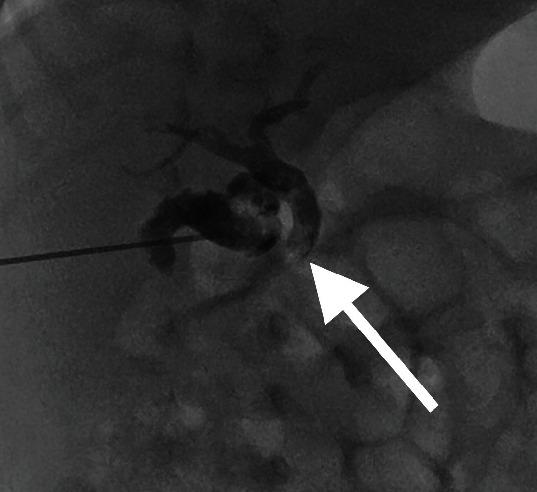

Inspissated bile syndrome is a rare cause of cholestatic jaundice in infancy, occurring due to obstruction of the biliary ducts and gallbladder by biliary sludge. Traditional methods of treatment include surgical drainage or cholecystostomy drain placement. Both can be associated with complications and prolonged admission. We present 2 cases treated with a single percutaneous needle puncture of the gallbladder followed by saline lavage. Two neonates presented with cholestatic jaundice and sonographic evidence of biliary sludge and dilation of the common bile duct. Single sonographic-guided needle puncture of the gallbladder was followed by irrigation with saline. Clearing of the biliary sludge was confirmed by sonography and cholecystocholangiography. There was resolution of the cholestatic jaundice, with no complications or repeat procedures.

浓缩胆汁综合征是婴儿期胆汁淤积性黄疸的一种罕见病因,由胆泥阻塞胆管和胆囊所致。传统治疗方法包括手术引流或放置胆囊造瘘引流管。这两种方法都可能伴有并发症且住院时间延长。我们报告2例通过经皮单针穿刺胆囊并随后进行盐水灌洗治疗的病例。两名新生儿出现胆汁淤积性黄疸,超声检查有胆泥及胆总管扩张的证据。在超声引导下对胆囊进行单针穿刺,随后用盐水冲洗。通过超声检查和胆囊胆管造影证实胆泥已清除。胆汁淤积性黄疸消退,无并发症且无需重复操作。